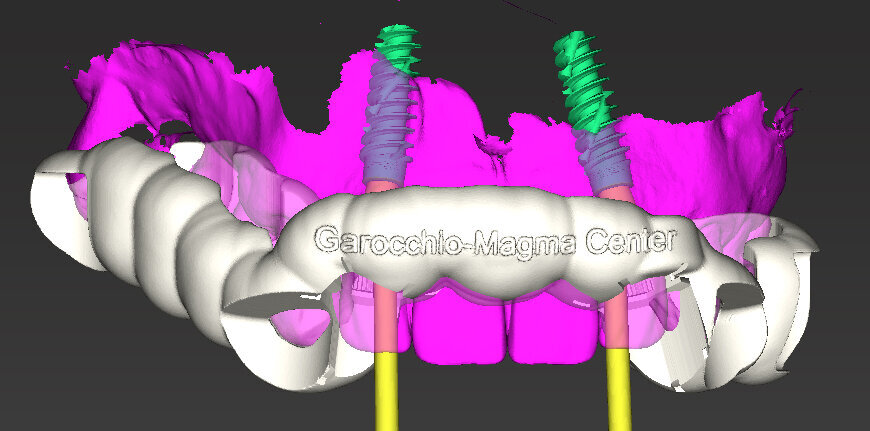

Dobbiamo quindi essere in grado, una volta definita la posizione corretta dell’impianto, di trasferire tutto clinicamente e di realizzare una fase chirurgica che possa rispettare tale programmazione. Voglio dunque ricavare dal progetto una dima chirurgica da utilizzare durante l’intervento: preparare il letto implantare e inserire l’impianto attraverso le guide consente di essere precisi e di realizzare l’intervento senza rischi. La dima chirurgica è realizzata attraverso stampanti 3D che oggi sono diventate molto affidabili. Le dime prodotte vengono controllate e posizionate su modelli stereolitografici ricavati dall’estrapolazione dei file STL direttamente da CoDiagnostiX, il software di chirurgia computer assistita di Dental Wings. La dima chirurgica adattata sul modello ci consente di verificarne, attraverso le finestre di ispezione, la congruità. Se la dima è precisa sul modello allora possiamo pensare di poter utilizzare lo stesso principio subito dopo il posizionamento implantare.

Il piano di trattamento prevede l’estrazione degli elementi dentali, l’inserimento di due impianti e la realizzazione di una protesi fissa di quattro elementi. Il problema da gestire è quello della fase provvisoria. Non è ipotizzabile una protesi mobile e quindi programmiamo di inserire subito dopo l’intervento un provvisorio immediato. Questo ci consente di condizionare da subito i tessuti periimplantari e anche le zone dei ponti. Si rileva un’impronta digitale (Figg. 5, 6), e la programmazione degli impianti viene effettuata con un software di chirurgia guidata (Fig. 7) e la posizione degli impianti nello spazio biologico e nello spazio protesico viene fatta sulla base di una ceratura diagnostica (Figg. 8, 9). Inseriamo gli impianti virtuali nell’osso disponibile (Figg. 10-13) e in relazione all’aspetto protesico correggiamo l’asse di inclinazione degli impianti con componenti secondarie angolate a 17° (Figg. 14, 15). Questo ci consentirà di realizzare una protesi avvitata con i fori situati nella zona palatale.

Il nostro obiettivo è quello di riuscire a dare alla paziente un provvisorio immediato nell’arco di due ore. Questo diventa possibile perché abbiamo utilizzato un flusso digitale fin dall’inizio. In laboratorio vengono realizzate la dima chirurgica (Figg. 16, 17), la dima protesica (Fig. 18) e anche il provvisorio (Figg. 19-21) che contiene delle alette di riposizionamento. Il tutto gestito con modelli digitali sui quali saremo in grado di funzionalizzare il provvisorio post-chirurgico (tecnica DIL). In un caso come questo se utilizziamo un flusso digitale possiamo evitare subito dopo la chirurgia di rilevare un’impronta degli impianti inseriti. Infatti, utilizziamo una dima chirurgica che ci faciliterà le fasi di intervento. La dima ci consentirà di non fare lembi e nessuna incisione di rilascio (Fig. 22), dopo aver inserito gli impianti (BLX Straumann) (Figg. 23-31) e aver controllato il loro alloggiamento, inseriamo sugli stessi dei transfert da impronta (Fig. 32).

Fig. 16 - Disegno dima chirurgica.

Fig. 19 - Modelli digitali relazionati.

Fig. 20 - Modello master di lavoro.

Fig. 21 - Modello Master e provvisorio pre-chirurgico.